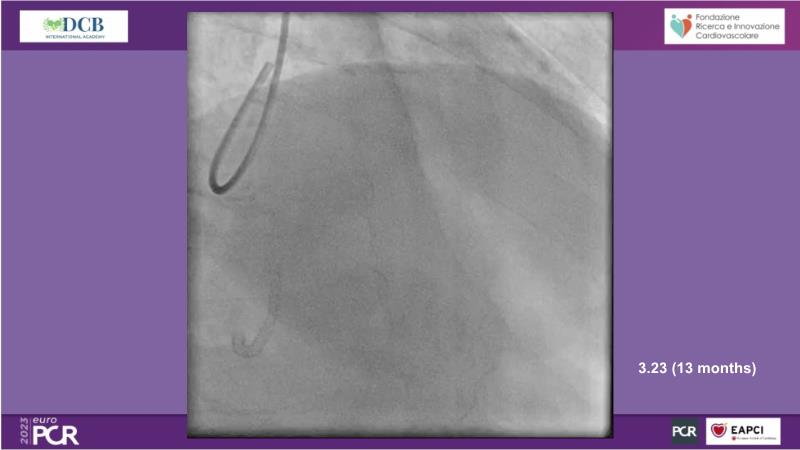

- To receive an in-depth insight into the latest clinical data and experiences on drug-coated balloon usage in in-stent restenosis, de-novo and bifurcation indications